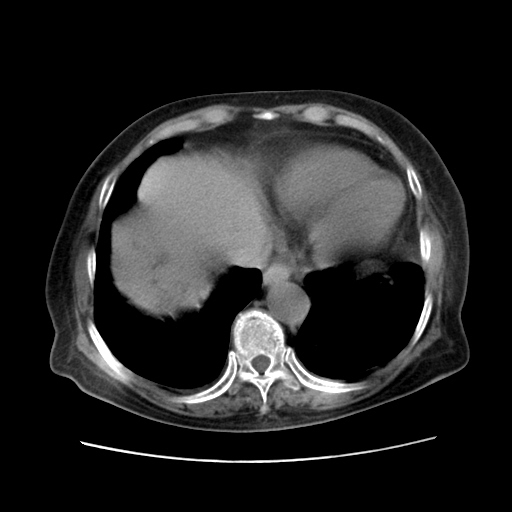

女,77.无不适

胆管扩张,壶腹部占位?

肝脏变异、异位胆囊,肝右叶肝内胆管结石并肝内胆管扩张。

肝内胆管扩张,胆囊炎,胆囊窝积液。 右侧胸腔少量积液。

肝右叶肝内胆管结石并肝内胆管扩张。